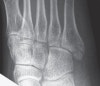

Cf) Flake fractures

Small flakes of bone are a common finding following trauma. The significance of these injuries depends on their anatomical location.

The fracture of 5th metatarsal base shown here is at the insertion point of the peroneus brevis tendon and is therefore potentially more significant than the fracture of the cuboid bone.